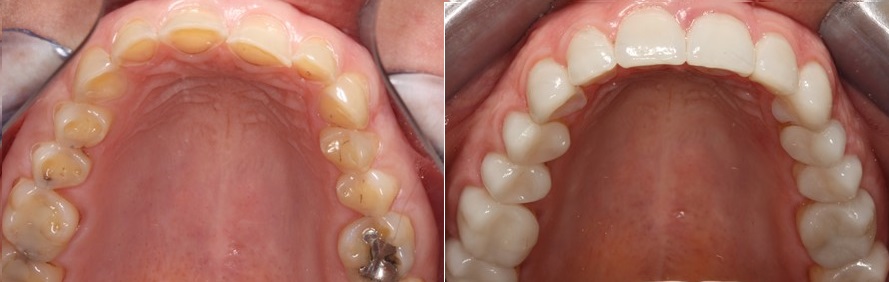

Η εικόνα των δοντιών της άνω γνάθου πριν και μετά την αποκατάσταση